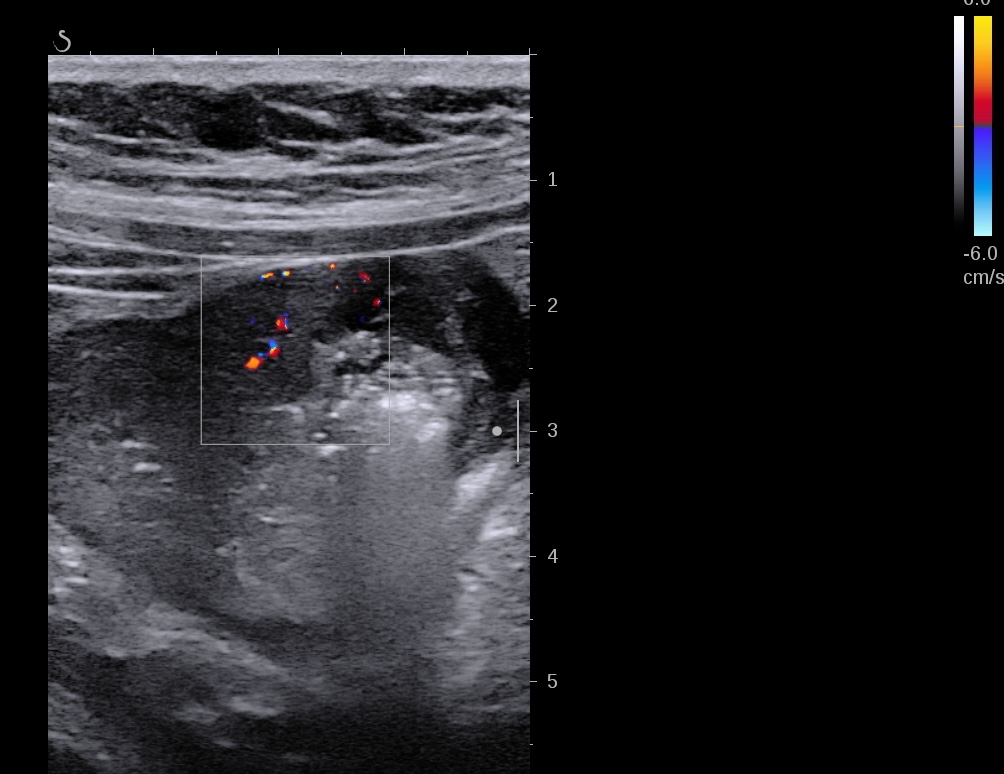

Epaississement entre 4.5 et 7 mm selon les segment, la structure en couche disparait totalement par endroit, à d’autre elle est partiellement conservée. Activité doppler intense de la paroi

Le Score de Milan (MUC) est à (1,4 x7+2) = 11,8

Là encore la paroi est très hypoéchogène, la structure en couches est par endroit totalement absente, ulcérations en surface, infiltration de la graisse, doppler intense, petites adénopathies périphériques.

Le rectum est bien vu avec la sonde basse fréquence la paroi atteint 10 mm à ce niveau.

Le score de Milan MUC est de (10 x1,4+2) = 16